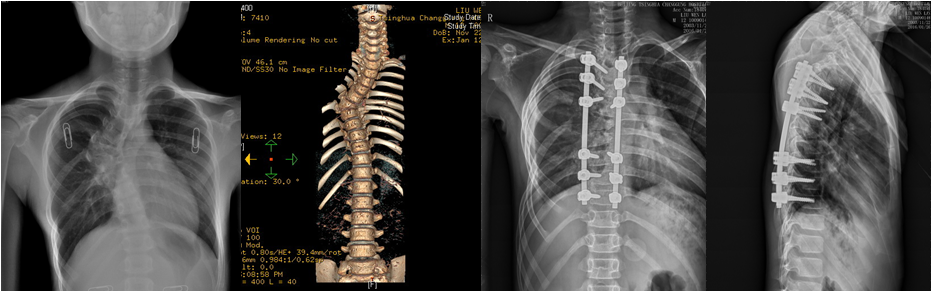

腰椎退行性侧弯伴间盘源性腰痛;减压矫形固定融合

而成人型脊柱侧弯,往往会伴随间盘突出、脊柱不稳、椎管狭窄,引起一系列脊髓和神经损害,如下肢疼痛、麻木、无力、不能行走、大小便功能障碍。治疗时需要综合考虑减压和矫形。

经完善三维影像学检查,脊柱专业组查房讨论,分别针对4例患者,制订个体化精准减压矫形方案,由肖嵩华教授主刀,宋飞主治医师和脊柱组医师配合,在连续的4个手术日,分别完成胸6半椎体切除胸廓成形矫形固定,腰椎后凸截骨矫形固定融合,退变性侧弯减压矫形固定融合,侧后凸减压截骨矫形融合固定,4台高难度手术均告成功。12岁的男孩是第一个接受手术的患者,男孩父母的心理压力非常大,待医师走出手术室,告知手术成功时,一直坚强的母亲眼泪瞬间流了下来,“这场手术把孩子的命运带回了正常的轨道。”

患者脊柱畸形得到纠正,伴随的椎管狭窄压迫神经等症状也得到彻底根治。困扰患者多年的躯干外形异常和神经功能障碍一去不复返。术后2-3天,4位患者均可下地,“腰杆子直起来了”;“大腿不疼不麻,能正常走路了”;“身高增加了”,脊柱畸形患者术后效果良好,可谓:新年开了个好头。